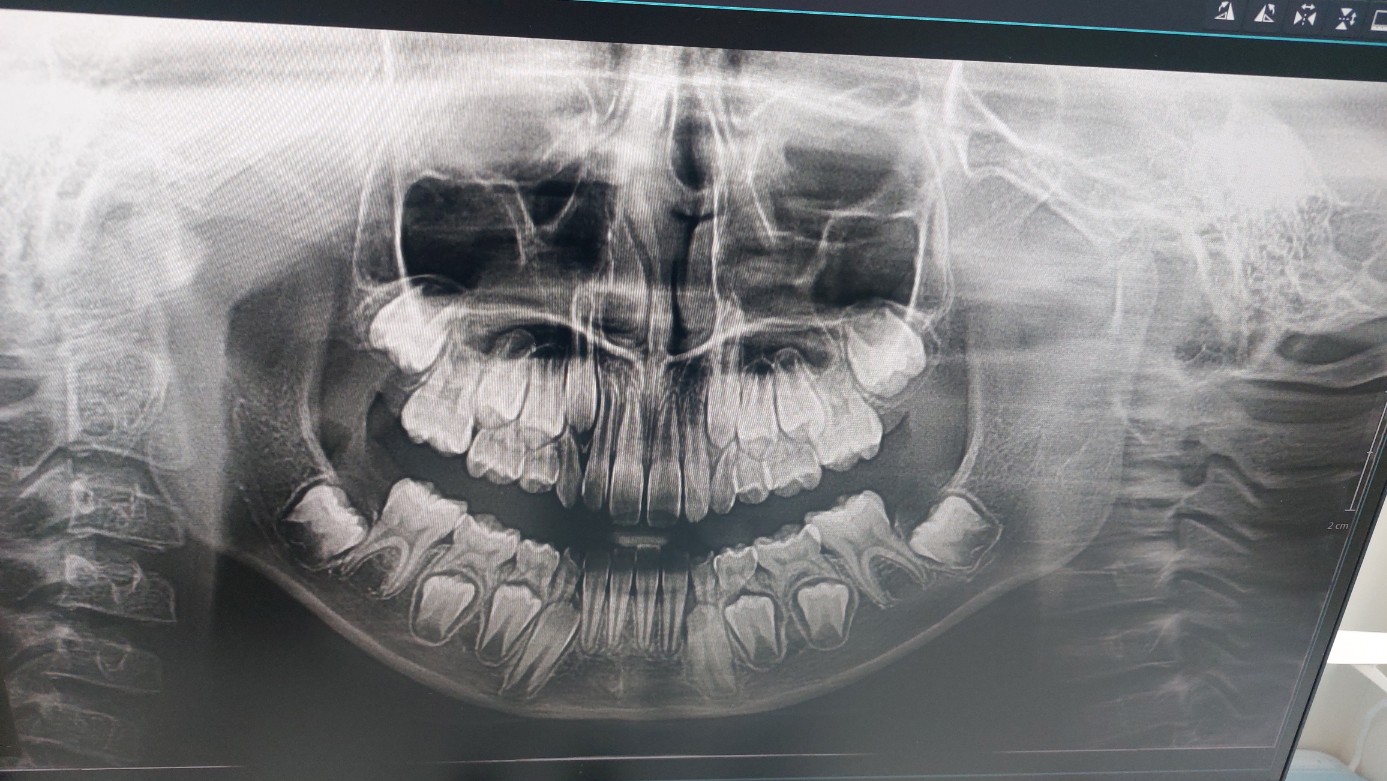

그러지 말고 내일 아침에 치과에 가보자며 모두 잠자리에 들어간다. 다음날 아침 일하는데 다래한테 전화가 온다. 올드이빨이 빠진 거다고.. 안심이다고.. 히히히 웃는다. 지난 텀에 치과 정기점검을 받았는데, 거기에 엄마가 연락해 보고 그때 촬영한 엑스레이 사진을 확인해줬다고 한다.

엑스레이 사진을 보니 아직도 빠져야 할 이빨이 많다. 놀랍게 오늘 저녁에도 이를 한 개 빼들고 나왔다. 어제 반대쪽이다. 겁 없는 소녀다. ㅎㅎㅎ